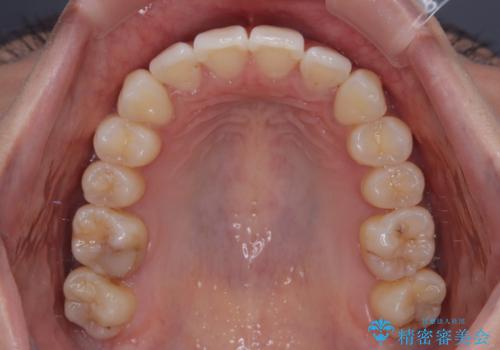

前に飛び出した上顎前歯をスッキリと引っ込める ワイヤー装置での矯正治療

横顔は元々突出した印象ではなかったのですが、上顎前歯の角度が改善したことで、唇の閉じにくさが改善されました。

抜歯矯正とするような歯列ではないため、舌のトレーニングを行いながら歯列を側方に拡大させることで口元の突出感を改善することとしました。